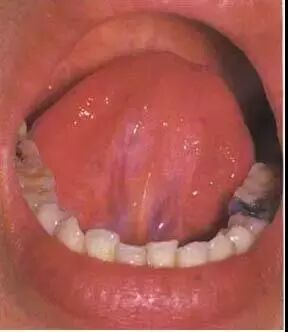

08

淡紫舌多见于阳虚阴盛之证。本图患者为肺原性心脏病,舌淡紫,苔薄白而湿润。提示阳气不足,血行不畅。